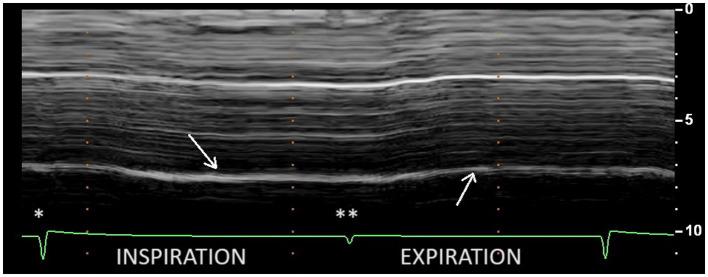

On paralyzed hemidiaphragm, thickening was less than 20% in all patients during deep inspiration. Thinning was recorded in 53% of cases. In some cases, the recording of the thickening could be difficult. The study of motion during voluntary sniffing reported a paradoxical excursion in all but one patient. During quiet breathing, an absence of movement or a paradoxical displacement was observed. During deep inspiration, a paradoxical motion at the beginning of inspiration followed by a reestablishment of movement in the cranio-caudal direction was seen in 82% of cases. In some patients, there was a lack of movement followed, after an average delay of 0.4 s, by a cranio-caudal excursion. Finally, in 4 patients no displacement was recorded. Evidence of hyperactivity (increased inspiratory thickening and excursion) of contralateral non-paralyzed hemidiaphragm was observed.